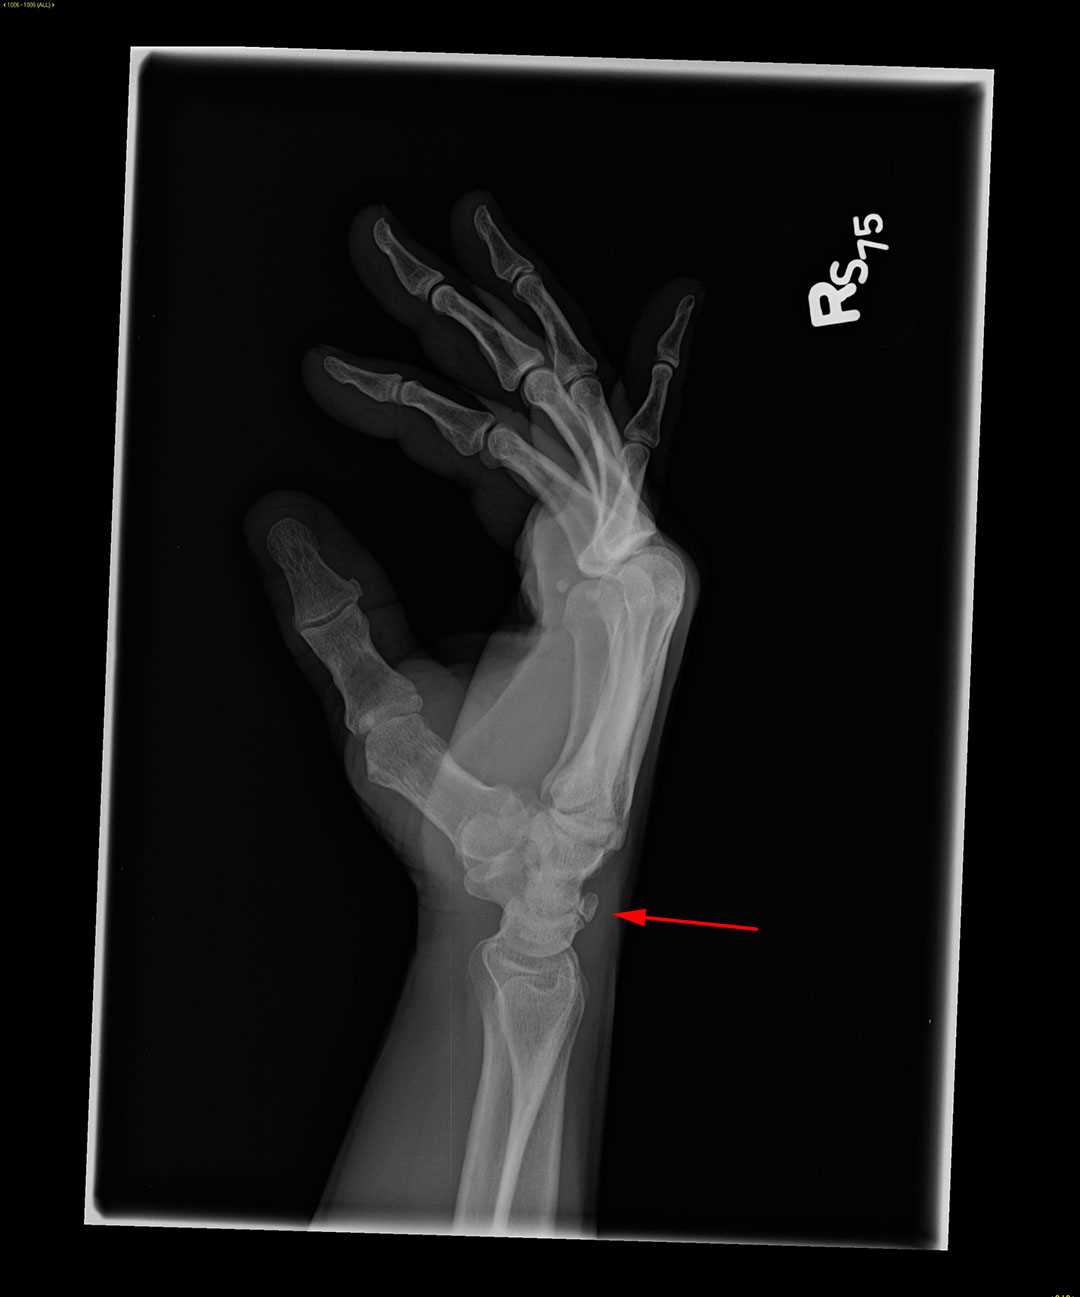

From www.mdedge.com

20yearold male college basketball prospect • wrist pain after falling Triquetrum Fracture X Ray Diagnosis is confirmed with orthogonal views of the wrist. Triquetral fractures are the most common carpal fracture after scaphoid fractures. Triquetrum fractures are common carpal fractures that are often associated with other injuries to the wrist. Although they are usually managed. It may be fractured by means of. Triquetrum fractures typically occur from a fall onto an outstretched arm with. Triquetrum Fracture X Ray.